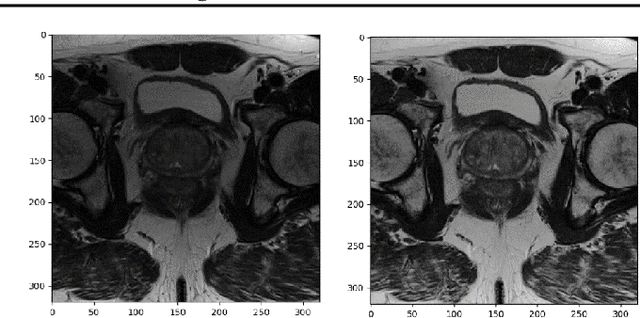

Multi-parametric magnetic resonance imaging (mpMRI) has a growing role in detecting prostate cancer lesions. Thus, it is pertinent that medical professionals who interpret these scans reduce the risk of human error by using computer-aided detection systems. The variety of algorithms used in system implementation, however, has yielded mixed results. Here we investigate the best machine learning classifier for each prostate zone. We also discover salient features to clarify the models' classification rationale. Of the data provided, we gathered and augmented T2 weighted images and apparent diffusion coefficient map images to extract first through third order statistical features as input to machine learning classifiers. For our deep learning classifier, we used a convolutional neural net (CNN) architecture for automatic feature extraction and classification. The interpretability of the CNN results was improved by saliency mapping to understand the classification mechanisms within. Ultimately, we concluded that effective detection of peripheral and anterior fibromuscular stroma (AS) lesions depended more on statistical distribution features, whereas those in the transition zone (TZ) depended more on textural features. Ensemble algorithms worked best for PZ and TZ zones, while CNNs were best in the AS zone. These classifiers can be used to validate a radiologist's predictions and reduce inter-reader variability in patients suspected to have prostate cancer. The salient features reported in this study can also be investigated further to better understand hidden features and biomarkers of prostate lesions with mpMRIs.